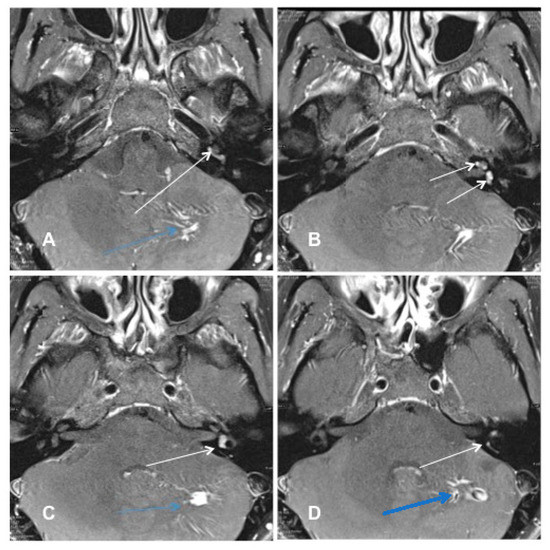

Patient #3 had a middle cochlear turn ILS (Figure 3) requiring subtotal cochleoectomy, meaning that parts of the modiolus had to be removed. One year after ILS removal and cochlear implantation, this patient scored 50% in FMT.

Figure 3. Case #3: ILS of the middle cochlear turn (A) MR image T1 VIBE with i.v. gadolinium: the white arrow points to the intracochlear schwannoma in the middle turn. (B) Intraoperative image of the subtotal cochleoectomy exposing the schwannoma (black arrow) in the middle turn. (C) Magnified image of the intracochlear schwannoma in the middle turn (black arrow). (D) Postoperative ConeBeam CT of the CI electrode (white arrow) in the cochlea.